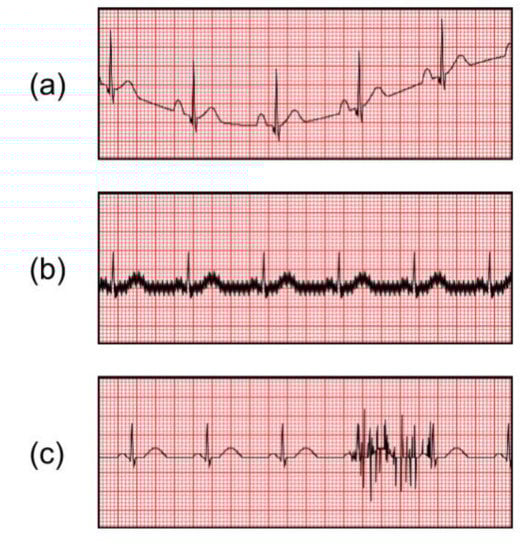

2.4. Abnormal ECG Signals